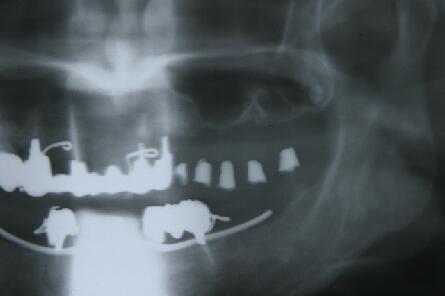

術前エックス線写真

上顎洞の下縁の骨が1~3ミリ程度しかなくソケットリフトでは不可能なのでサイナスリフトの選 択となる